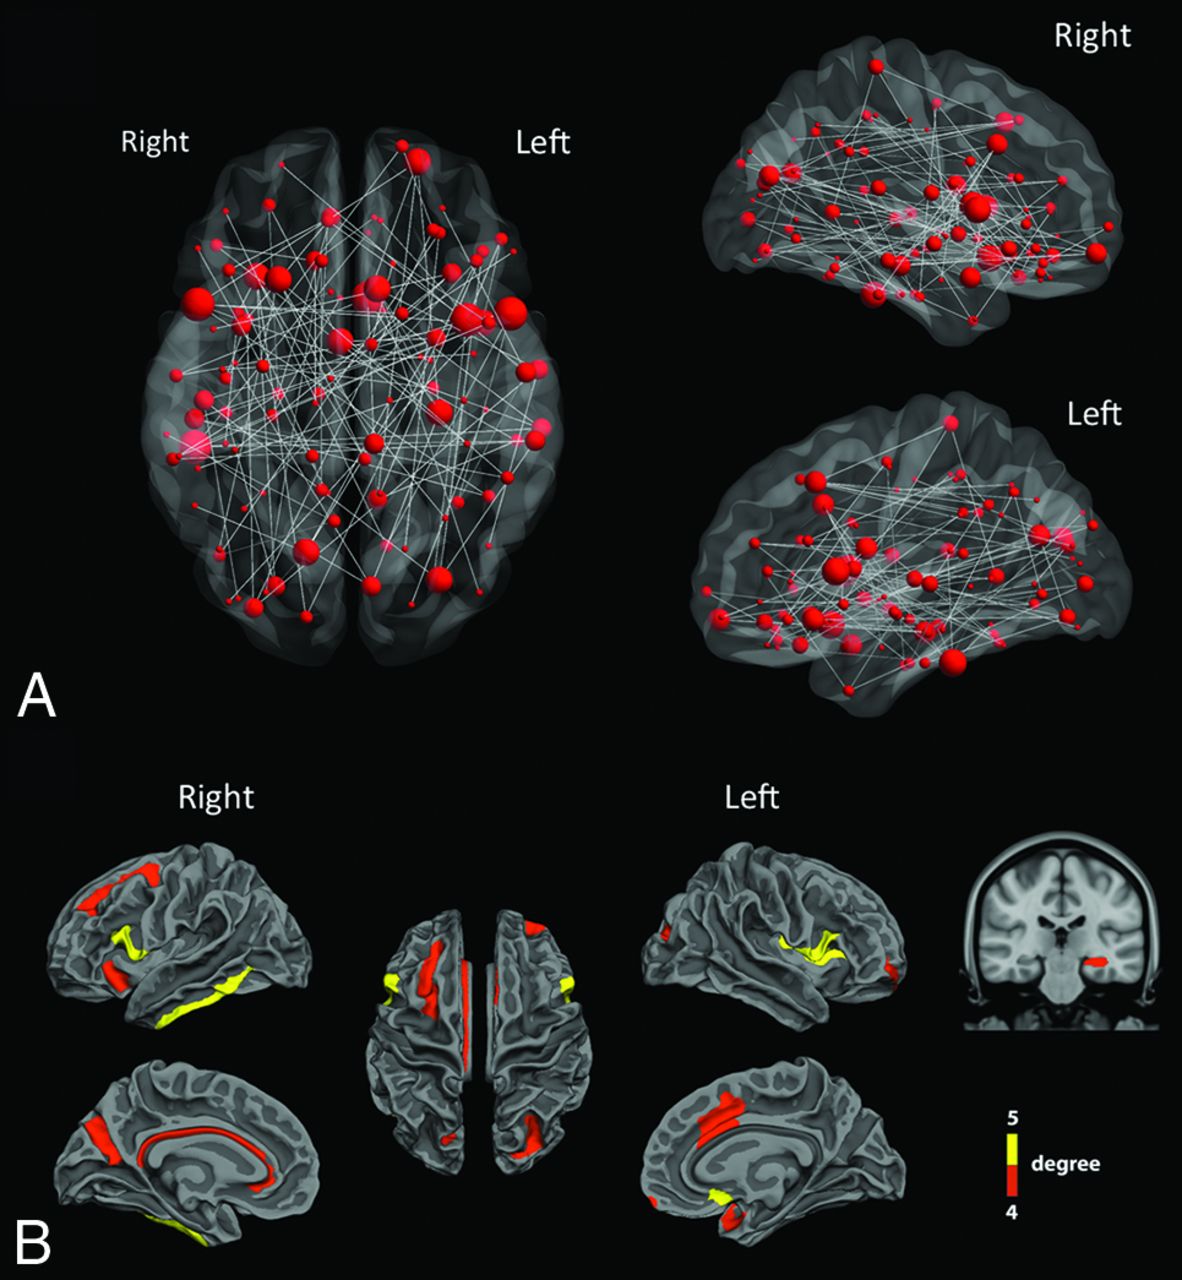

In comparison with controls, a cluster of 113 nodes and 114 connections (33 left intrahemispheric, 31 right intrahemispheric, and 50 interhemispheric connections) had significantly decreased structural connectivity (ie, decreased number of fiber tracts) (P < .05 NBS corrected, t values ranging from 3.03 to 8.73) in patients with TGA at acute phase (Fig 2A and On-line Table).

Altered structural connections in patients with TGA. A, Structural connectivity differences between controls and patients with TGA at acute phase. The gray lines mean significant decrease of connectivity in patients compared with controls. The red dots represent the location of ROIs and their size is proportional to the number of significant connections. A network of 113 ROIs and 114 connections had significantly decreased structural connectivity in patients with TGA (P < .05 NBS corrected, t-values ranging from 3.03–8.73). B, In this widespread network, the cortical and subcortical regions (nodes) with a number of significantly altered connections between patients and controls greater than 4 were mainly located in inferior and mesial temporal, cingulate, and frontal cortices.

In this widespread network, structural changes in patients with TGA were more prominent in core regions (ie, showing the highest number of altered connections) including: left hippocampus, left frontomarginal gyrus and sulcus, left middle anterior part of the cingulate gyrus and sulcus, left subcallosal gyrus, left planum polare of the superior temporal gyrus, left superior segment of the circular sulcus of the insula, left superior and transverse occipital sulci, left and right opercular part of the inferior frontal gyri, right inferior temporal gyrus, right anterior segment of the circular sulcus of the insula, right superior frontal sulcus, right parieto-occipital sulcus, and right pericallosal sulcus (Fig 2B).